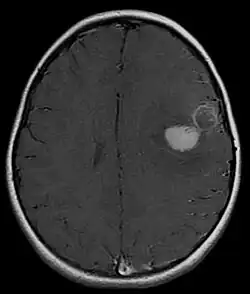

The approach to management of a CNS PNET is first to obtain detailed imaging through MRI, as well as additional scans of the patient's body (X-ray, CT, PET, even bone marrow biopsies) to look for metastasis or other associated malignancies. The tumor will then need to be biopsied to confirm the diagnosis. After the diagnosis of a CNS PNET is confirmed, management includes neoadjuvant chemotherapy and radiation (to reduce tumor size burden), complete surgical resection with confirmed negative margins, and/or additional adjuvant post-surgical chemotherapy. CNS PNET is aggressive and must be managed as so. Palliative care services should also become involved in the patient's care team when the diagnosis is made. [6]